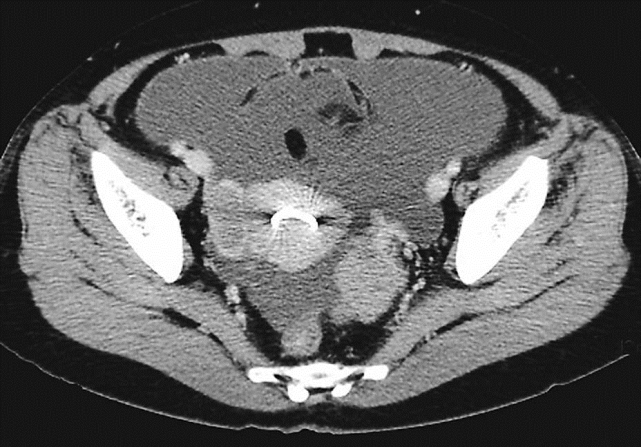

卵巢恶性肿瘤CT检查

盆腔内子宫两侧见不规划软组织肿块影,增强扫描病灶轻中度强化改变,盆腔、腹腔内见积液,宫腔内见环影